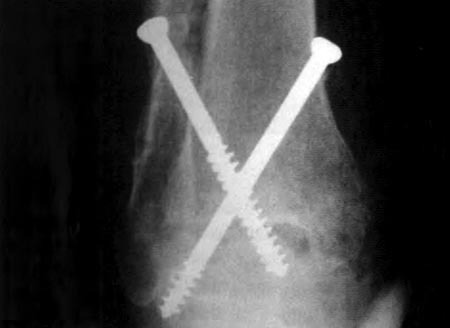

Se utilizaron, en 13 casos, tornillos canulados (Fig 5 a y b) de 7 mm de diámetro con arandelas y la ayuda del intensificador de imágenes para corroborar la posición de los tornillos, evitando que violen la articulación subastragalina. Estos son colocados en forma cruzada, desde la tibia, con dirección posteroanterior hacia el centro del cuerpo del astrágalo, con una angulación de 45° con respecto al eje tibial, realizando compresión entre las superficies cruentadas, ajustando los tornillos en forma alternada. En dos casos en que no se contó con tornillos canulados se utilizó tornillos de esponjosa de 6,5 mm En el caso restante se colocó un tutor externo clásico de Charnley tambien con buen resultado.

Figura 5a: pos. op. frente

Figura 5b: pos. op. perfil

Consolidación 8 semanas